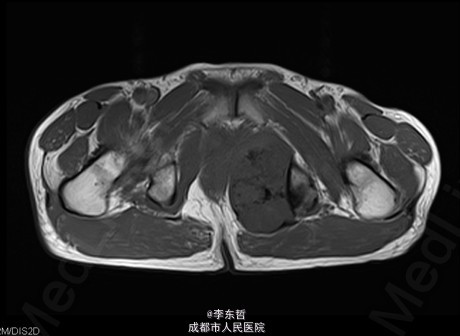

查体:臀部、会阴部、下腹部未触及包块,左下肢前内侧皮肤感觉较对侧减弱,双侧膝反射、跟腱反射正常引出,肛周皮肤感觉减退,直肠指检可触及质韧包块,活动度较差。双下肢肌力5级,双下肢各关节活动度可。 辅查:外院增强CT示:盆腔左侧壁见团块状软组织密度影,密度不均,其内见多发斑块高密度影,病灶大小约9.4*7.6cm,增强后强化不明确。我院X片示:左侧闭孔及耻骨区见不均匀高密度影,大小约6.2*6.7cm。我院MRI示:盆腔左份见长T1长T2肿块影,大小约10.3*7.7*10.5cm,向前推挤膀胱,向右推挤前列腺。我院骨扫描显示:耻骨联合及左侧耻骨支核素浓集。